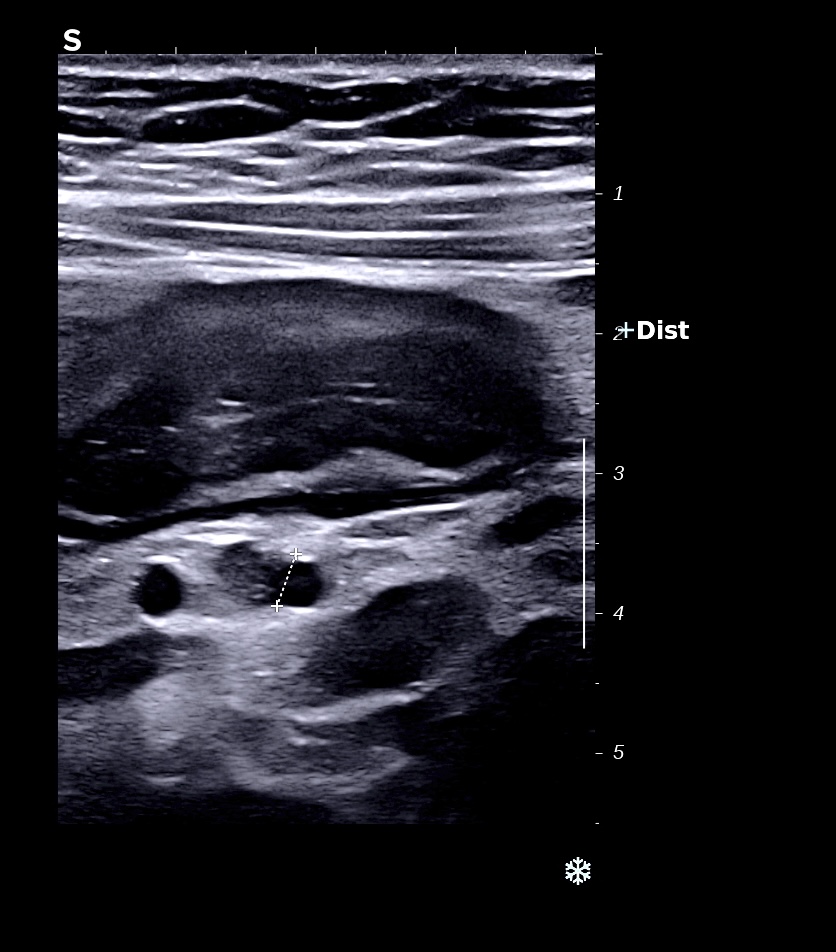

RCH classique, respect de la structure en couche,sous muqueuse très épaissie; musculeuse intacte

Classiquement dans la RCH, l'épaississement concerne les couches 2 et 3, c'est à dire muqueuse (hypoéchogène) et sous muqueuse (hyperéchogène) car il s'agit d'une maladie superficielle de la paroi, la musculeuse (4 ième couche hypoéchogène) est intacte et donc le bord externe est linéaire et régulier

L'épaississement prédomine à la 3 ième couche hyperéchogène (qui fait > 1/3 de la paroi)

Perte des haustrations (le bord externe du colon est rectiligne, lors de la cicatrisation on retrouve des haustrations)

L'épaississement prédomine à la 3 ième couche hyperéchogène( > 1/3 de la paroi), il est continue, régulier, cironférentiel

La structure en couche est conservée